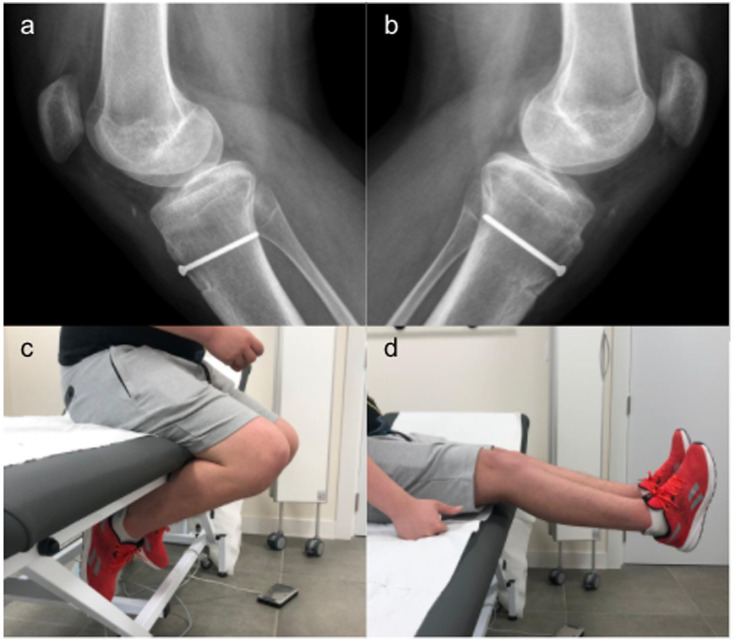

胫骨前结节骨折撕脱是一种不常见的损伤。同时伴有髌骨断裂的情况更是罕见。我们报告了一名 14 岁男性患者的病例,他双侧胫骨前结节骨折,同时伴有双侧髌腱完全断裂。青春期、运动量和高体重指数可能是造成这种并发双侧损伤的原因。两处损伤均采用一期修复手术进行治疗,使用插管皮质螺钉对胫骨结节进行切开复位和内固定,并按照克拉科夫技术对肌腱进行初步缝合。据作者所知,迄今为止还没有其他文献报道过双侧均有病变的病例。

Anterior tibial tuberosity fracture avulsion is an uncommon injury. A concomitant patellar rupture is even more scarcely encountered. We report the case of a 14-year-old male patient who suffered bilateral anterior tuberosity fractures with concomitant bilateral complete patellar tendon rupture. Adolescence, athletic activity, and high BMI may have contributed to this concomitant bilateral injury. Both lesions were treated in a one-stage repair surgery, performing an open reduction and internal fixation of the tibial tuberosity with a cannulated cortical screw and a primary tendon suture following the Krakow technique. To the authors' knowledge, no other cases of bilateral presentation of both lesions have been reported so far in the literature.